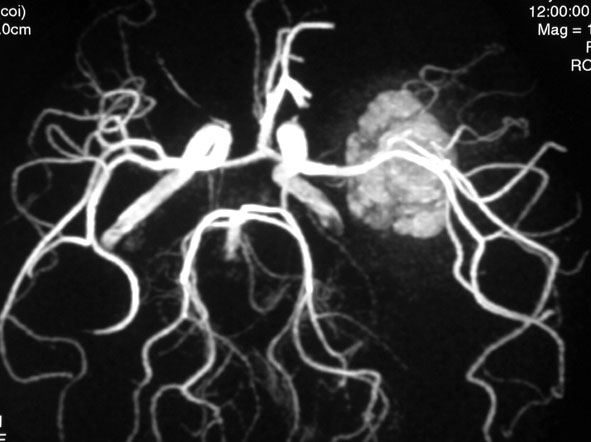

静脈性血管腫(静脈奇形)の合併を見つける方法

左は脳出血のCTです。海綿状血管腫からの出血を疑ったので造影のMRI(右の写真)をしました。血腫の周りに細い線がたくさん見えます。これが静脈奇形(静脈性血管腫)です。脳血管撮影DSAをしなくてもこの合併はわかるのです。この静脈奇形を手術で傷つけるとかなり広い範囲で脳梗塞がおきる可能性があります。